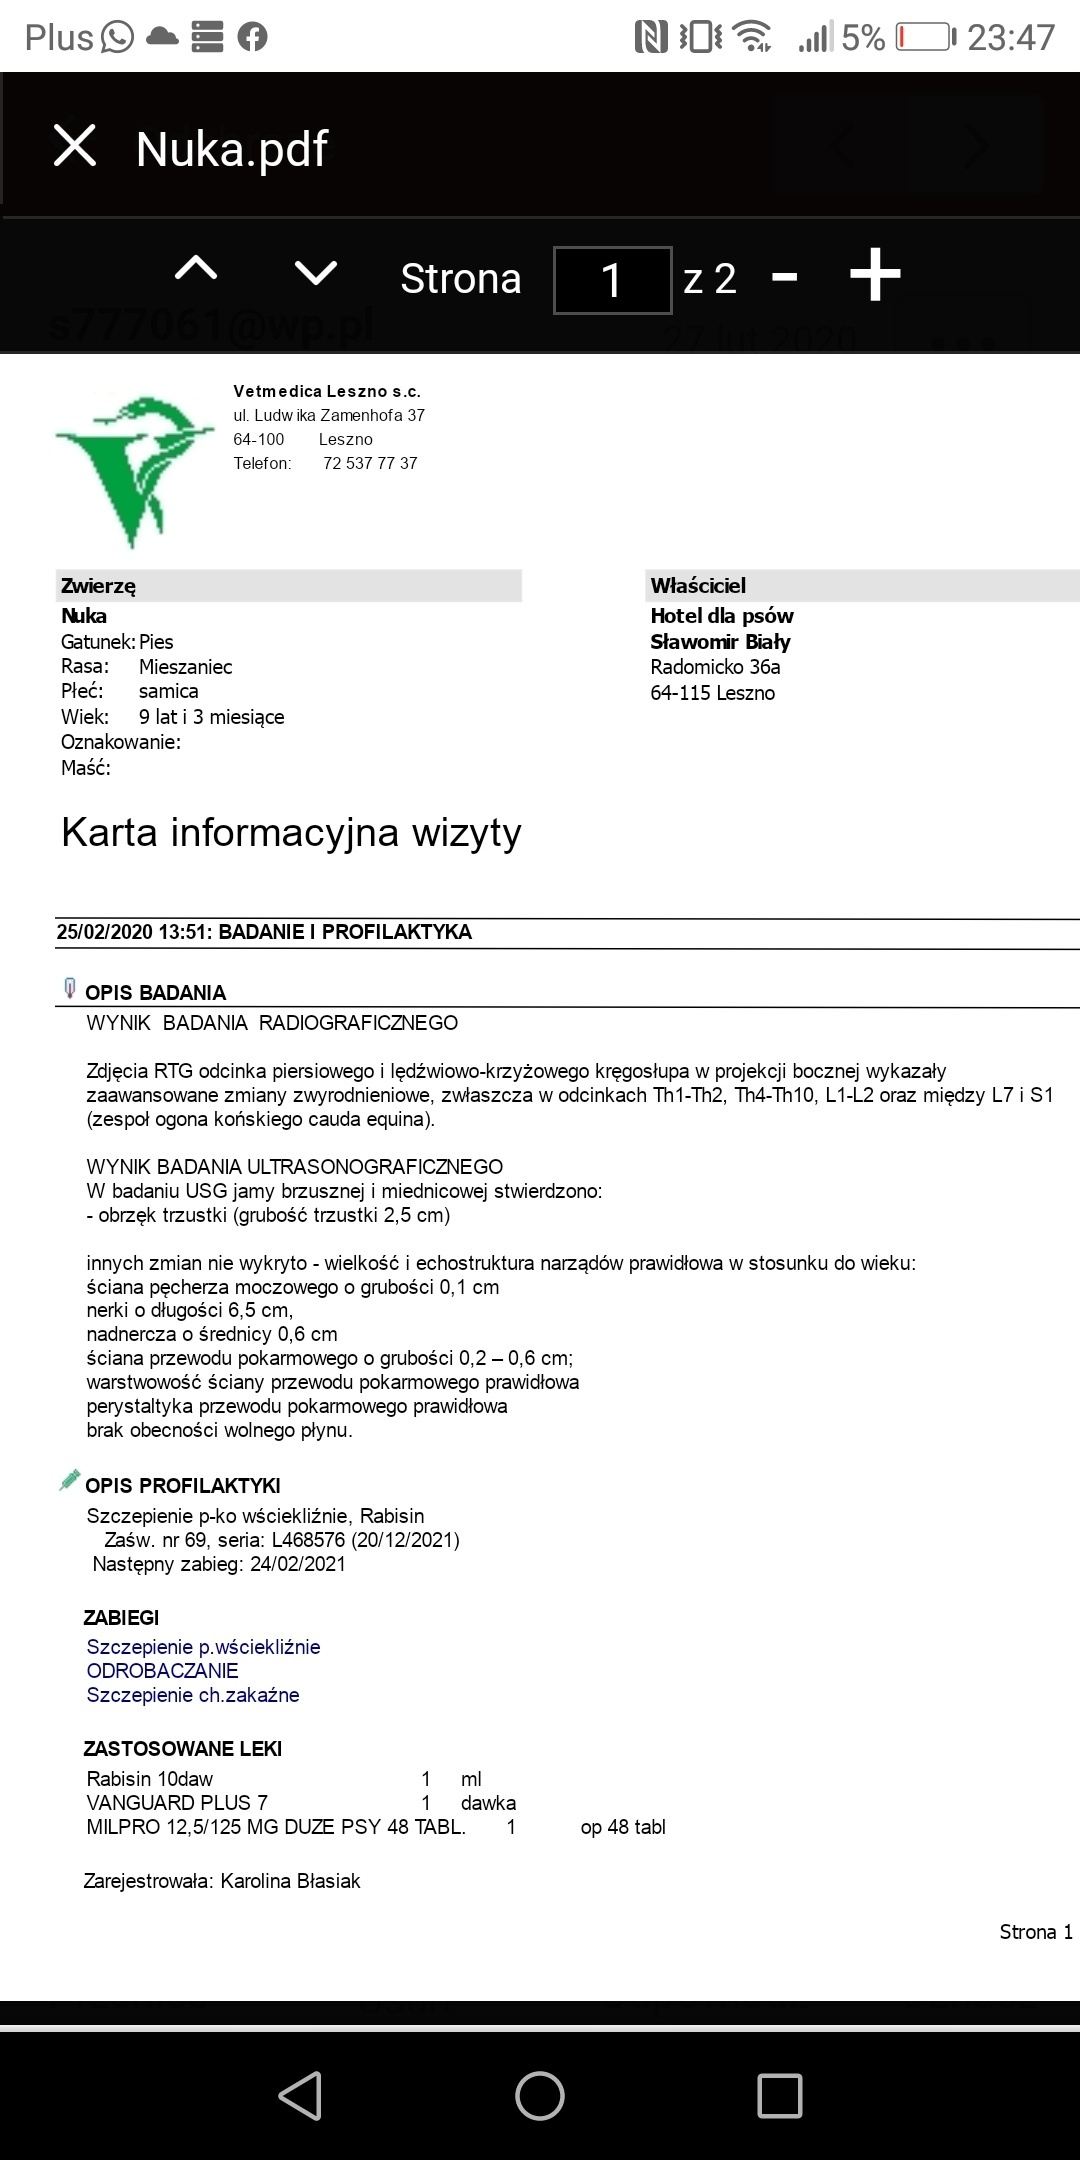

Kochani ta zbiórka jest założona na utrzymanie i leczenie suni Nuki zabranej z fatalnego przytuliska do hotelu by nie trafiła do schroniska. W hotelu przebywa już prawie 4 lata. Jest już starsza sunia... Takie psiaki maja małe szanse na adopcję. Dodatków problemem Nuki było nieakceptowanie małych dzieci. Nie mogliśmy jednak pozwolić by zginęła w schronisku. Czas nie oszczędza jednak Nuki i poglebily się problemy zwyrodnieniowe oraz doszło zapalenie trzustki. Nuka by żyć bez bólu musi dostawać lek o nazwie cimaglex 80 mg. Miesięczny koszt leczenia to 200 zł. Do tego musi jeść karmę niskotłuszczowa dla trzustkowcow. Koszt karmy takiej weterynaryjnej to ok. 250 zł.

NA zdj fakturka jeszcze za badania i szczepienie